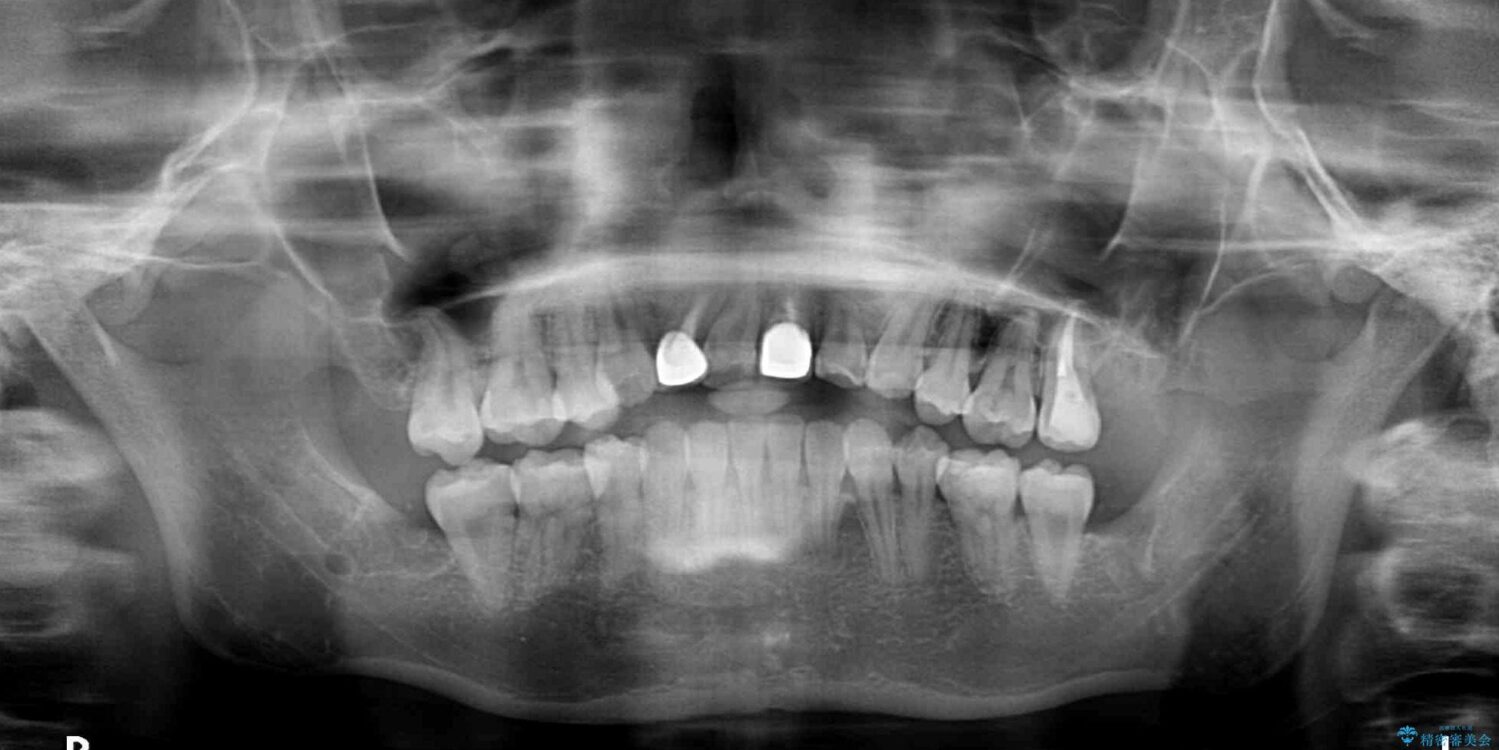

上顎親知らず周辺の炎症と、神経組織の失活した歯の炎症による痛みが認められたため、親知らずの抜歯と根管治療を行いました。

根管治療を行った歯はクラウンによる補綴治療が必要となりますが、高校生の頃に行った矯正治療の後戻りも気になるとのことで、補綴治療を行う前に矯正治療を行うこととしました。

後戻りは軽度であり、インビザラインにて歯列を整え、その後にオールセラミッククラウンにて補綴治療を行うこととしました。